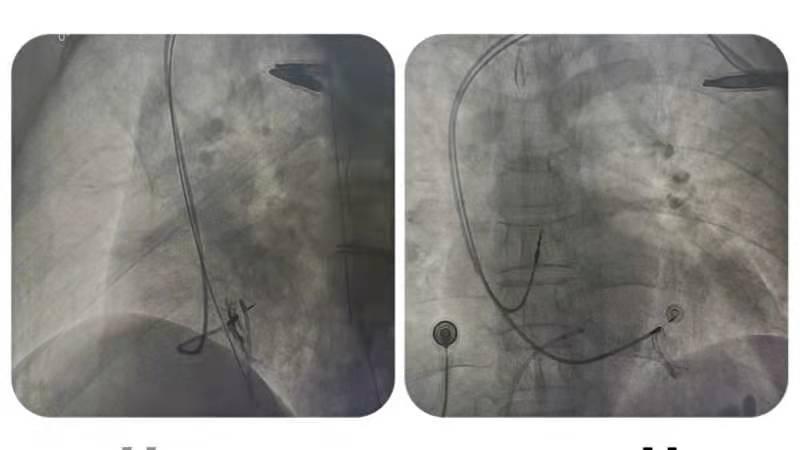

手术中,从右心室间隔侧将电极旋入左心室内膜下的左束支区域,成功实施了“左束支起搏”,左束支电位明显、术前心电图QRS波群从137ms变为术后心电图QRS波群106ms(QRS波群从宽到明显变窄),起搏各参数满意、电极固定牢固,手术圆满成功。

“左束支区域起搏相对于传统起搏方式最大的区别在于起搏左束支区域,激动沿束支下传,保持左室收缩同步。”据王福军介绍:对于缓慢型心律失常而言,常规的起搏位点无论是右室心尖部还是间隔部,均不是通过传导系统下传激动,因而人为造成了心室收缩不同步,导致有害的血流动力学效应,包括较高的房颤发生率、心力衰竭住院率和全因死亡率,虽然间隔部起搏相比心尖部起搏而言相对生理,且QRS波相对较窄,但无论右室间隔面起搏或左室间隔面起搏,均没有夺获传导束,与穿间隔至左室间隔心内膜下夺获传导束的左束支区域起搏有着本质差别,左束支区域起搏避免传统起搏方式导致的各心腔不同步,减少起搏器相关心力衰竭等不良临床事件。开展左束支区域起搏技术,需要在DSA平板显影及多导电生理仪指导下精确找到患者自身的希氏束传导系统,并通过DSA二维平面显影将一根仅4F粗细的电极精准旋入患者原有传导径路上,从而使电刺激信号通过该路径向下传导,这个难度无异于针孔穿线。